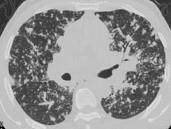

问题 男,38岁,咳嗽,咳痰,关节疼痛,外周淋巴结肿大,结合CT图像,最可能的诊断是 ( )

选项 A.肺泡蛋白沉积症 B.肺间质病 C.结节病 D.肺结核 E.霍奇金病

答案 C